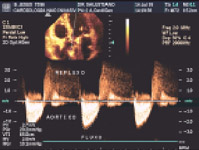

O ecocardiograma surgiu no cenário clínico a partir da década de 70 e permite a avaliação da estrutura anatômica e funcional do coração. Entretanto, somente com a incorporação das técnicas de Doppler (pulsado e contínuo), no início dos anos 80, foi possível fazer uma análise qualitativa do fluxo sangüíneo e das pressões intracardíacas (refluxos, shunts, gradientes etc), tornando esse método indispensável para uma avaliação completa do coração.

3.2 Ecocardiograma com Doppler Colorido

Esta modalidade de exame ecocardiográfico consagrou-se como fundamental no avanço da cardiologia e teve seu assentamento clínico no meados da década de 80. O ecocardiograma com Doppler em Cores, como é chamado, constitui o mais sensível recurso não invasivo (sem necessidade de contraste) para a observação do fluxo sangüíneo e sua dinâmica dentro das câmaras cardíacas e vasos. Este método atualmente é de eleição e indispensável para uma completa avaliação de patologias cardíacas que causam sopros e/ou shunts (valvulopatias, cardiopatias congênitas etc.).

O termo "em cores", que pode sugerir equivocadamente uma relação com efeitos "cosméticos" dispensáveis ao diagnóstico, remete, pelo contrário, as informações essenciais para se avaliar a severidade de cardiopatias que cursam com o distúrbio do fluxo sangüíneo. Assim, é importante que na solicitação desse recurso diagnóstico seja utilizado o termo em Cores, isto é, Ecocardiograma com Doppler em Cores.